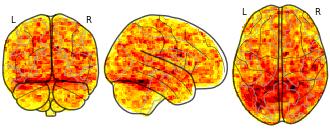

Measurement Invariance: Monetary Incentive Delay Task: subs 32 effect...

EmailClick to copy linkLink copied Cite(2023). Measurement Invariance: Monetary Incentive Delay Task: subs 32 effect onesample contrast Lgain Neut stat cohensd sample ABCD type site19 [Dataset]. http://identifiers.org/neurovault.image:805365niftiAvailable download formatsUnique identifierhttps://identifiers.org/neurovault.image:805365Dataset updatedOct 27, 2023License

Cite(2023). Measurement Invariance: Monetary Incentive Delay Task: subs 32 effect onesample contrast Lgain Neut stat cohensd sample ABCD type site19 [Dataset]. http://identifiers.org/neurovault.image:805365niftiAvailable download formatsUnique identifierhttps://identifiers.org/neurovault.image:805365Dataset updatedOct 27, 2023LicenseCC0 1.0 Universal Public Domain Dedicationhttps://creativecommons.org/publicdomain/zero/1.0/

License information was derived automaticallyDescriptionsubs-32_effect-onesample_contrast-Lgain-Neut_stat-cohensd_sample-ABCD_type-site19.nii.gz

Collection description

This collection includes the output files, z- and/or t-statistics (uncorrected), cohen-s D statistical maps (calculated: t-statistic / sqrt(n)) for subjects from the Adolescent Brain Cognitive Development (ABCD), Adolescent Health Risk Behavior (AHRB) and Michigan Longitudinal Sample (MLS). The analyses are for the modified monetary incentive delay task. ABCD and AHRB are multiband acquisitions (TR = 800ms, vox = 2.4mm; MB factor = 6). MLS is a spiral acquisition (TR = 2000ms; vox = 4mm). All datasets were preprocessed using fMRIprep v23.1.0 (fmap correction in AHRB/ABCD and no slice-time correction; MLS no fieldmap correction with slice-time correction).

For ABCD, AHRB and MLS, the following [six[ contrasts types are included for the anticipation phase (*_contrast-[type]*):

Lgain-Neut: Large Gain ($5) > Neutral (no money at stake)

LSgain-Neut: Large Gain ($5, .5) & Small Gain ($0.20, .5) > Neutral (no money at stake)

Lgain-Lloss: Large Gain ($5) > Large Loss (-$5)

Lloss-Neut: Large Loss (-$5) > Neutral (no money at stake)

LSloss-Neut: Large Loss (-$5, .5) & Small Loss (-$0.20, .5) > Neutral (no money at stake)

Lloss-Lgain: Large Loss (-$5) > Large Gain ($5)For the ABCD (N = 346) , AHRB (N = 97) and MLS (N = 112) there are group level contrasts for each of the two runs, e.g. *_type-run-01.nii.gz, *_type-run-02.nii.gz. For ABCD samples maps are included across different scanners and sites. Maps include site specific (e.g, *_type-site06.nii.gz) and scanner specific (e.g, *_type-SIEMENS.nii.gz) maps. Note, the N for each map is indicated in the first field, e.g subs-347 the sample size N = 347.

Subject species

homo sapiens

Map type

Other